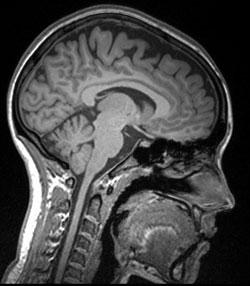

Resultado de la resonancia magn tica nuclear

Resonancia magn tica nuclear